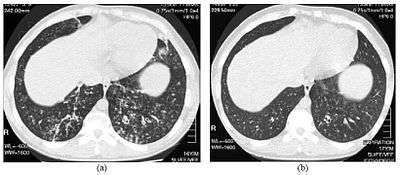

| High resolution computed tomography images of the lower chest in a 16-year-old boy with diffuse panbronchiolitis | |

The diagnosis of DPB requires analysis of the lungs and bronchiolar tissues, which can require a lung biopsy, or the more preferred high resolution computed tomography (HRCT) scan of the lungs.[7] The diagnostic criteria include severe inflammation in all layers of the respiratory bronchioles and lung tissue lesions that appear as nodules within the terminal and respiratory bronchioles in both lungs.[4] The nodules in DPB appear as opaque lumps when viewed on X-rays of the lung, and can cause airway obstruction, which is evaluated by a pulmonary function test, or PFT.[6] Lung X-rays can also reveal dilation of the bronchiolar passages, another sign of DBP. HRCT scans often show blockages of some bronchiolar passages with mucus, which is referred to as the "tree-in-bud" pattern.[7] Hypoxemia, another sign of breathing difficulty, is revealed by measuring the oxygen and carbon dioxide content of the blood, using a blood test called arterial blood gas. Other findings observed with DPB include the proliferation of lymphocytes (white blood cells that fight infection), neutrophils, and foamy histiocytes (tissue macrophages) in the lung lining. Bacteria such as H. influenzae and P. aeruginosa are also detectable, with the latter becoming more prominent as the disease progresses.[4][5] The white blood, bacterial and other cellular content of the blood can be measured by taking a complete blood count (CBC). Elevated levels of IgG and IgA (classes of immunoglobulins) may be seen, as well as the presence of rheumatoid factor (an indicator of autoimmunity). Hemagglutination, a clumping of red blood cells in response to the presence of antibodies in the blood, may also occur. Neutrophils, beta-defensins, leukotrienes, and chemokines can also be detected in bronchoalveolar lavage fluid injected then removed from the bronchiolar airways of individuals with DPB, for evaluation.[4][9]